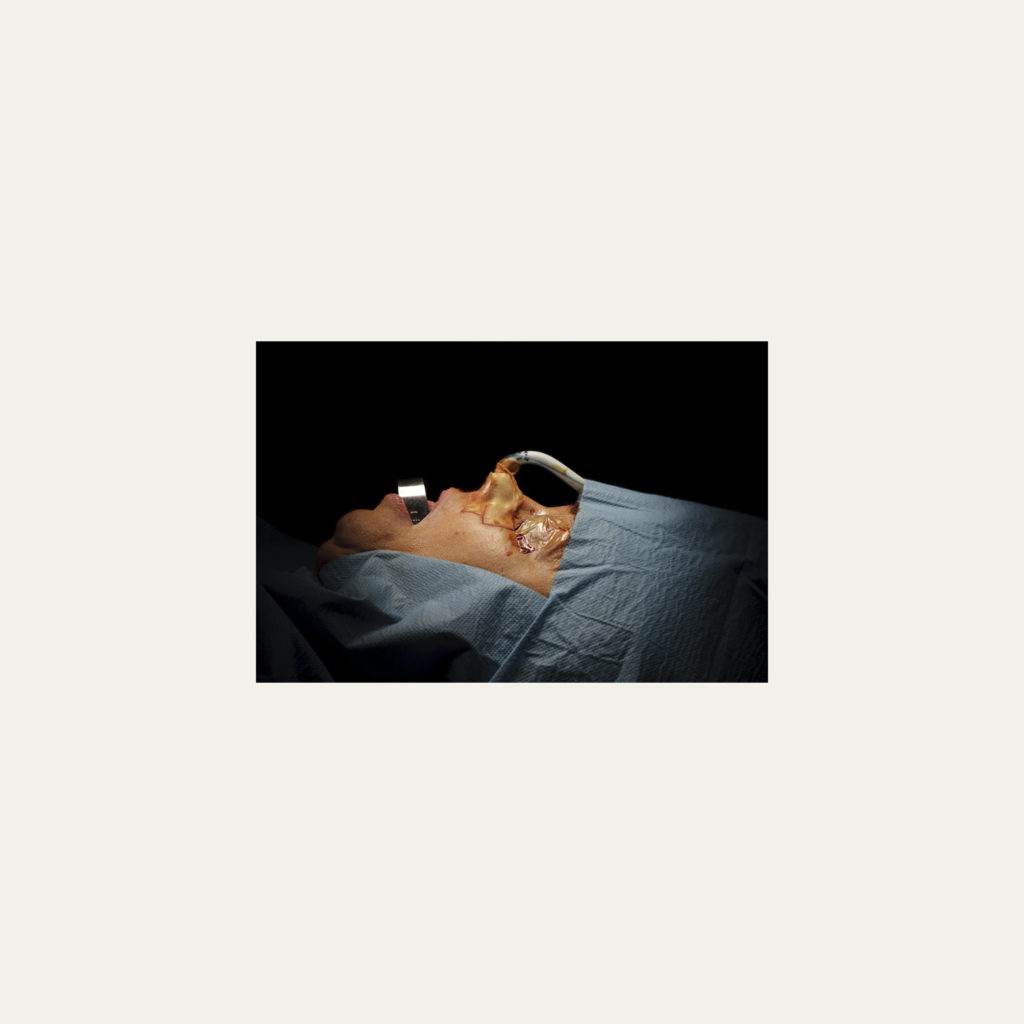

« Nature Morte » est la recherche de l’instant, pendant une intervention chirurgicale où la tête du patient opéré se retrouve seule dans le champ photographié. Aucune main intervenant, peu d’instruments chirurgicaux visibles, laissent le fragment de corps opéré existé pour lui-même. Les têtes, ainsi isolées, en deviennent presque des objets.

Cette approche est intensifiée par la présentation : dans de grands cadres carrés et passe-partout blancs, les photos de petit format font référence aux papillons épinglés de la collection d’un entomologiste.

Face à ces images, une forme de recueillement est nécessaire, s’approcher doucement pour s’approprier tous les détails des images.

Le caractère éminemment esthétique est souligné/donné par les gammes de couleur, la lumière précise sur la tête photographiée, les brillances partielles, renforçant également l’aspect pictural, les textures réelles.

L’humain présent dans ces images est celui qui rompt avec l’invisible et donne à voir l’architecture même de sa chair.